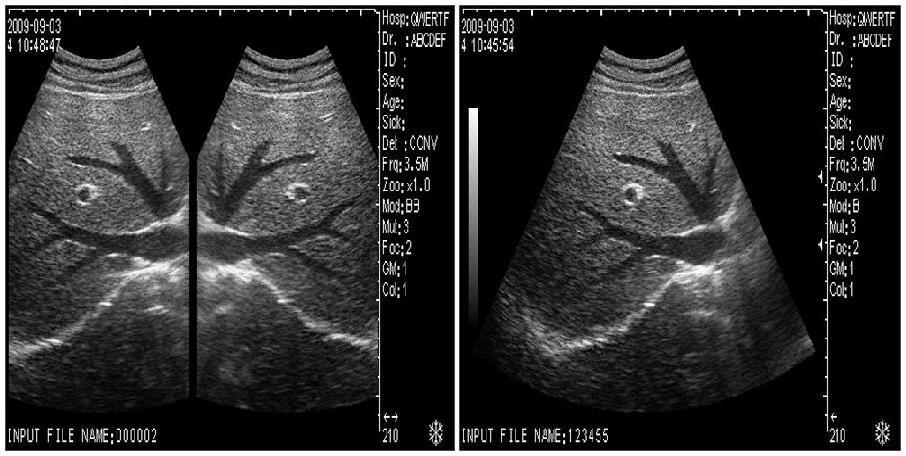

Model: RUS-6000V

Display modes: B, B+B, B+M, M, 4B

Display/ Monitor/ Screen: 10.1â high-resolution TFT LCD

Multi-frequency: Image magnification: x0.8, x1.0, x1.2, x1.5, x2.0

Pseudo color processor:7 color: Video output: PAL-D, VGA . USB port

Optional: linear/transvaginal/micro-cardiac/rectal/printer